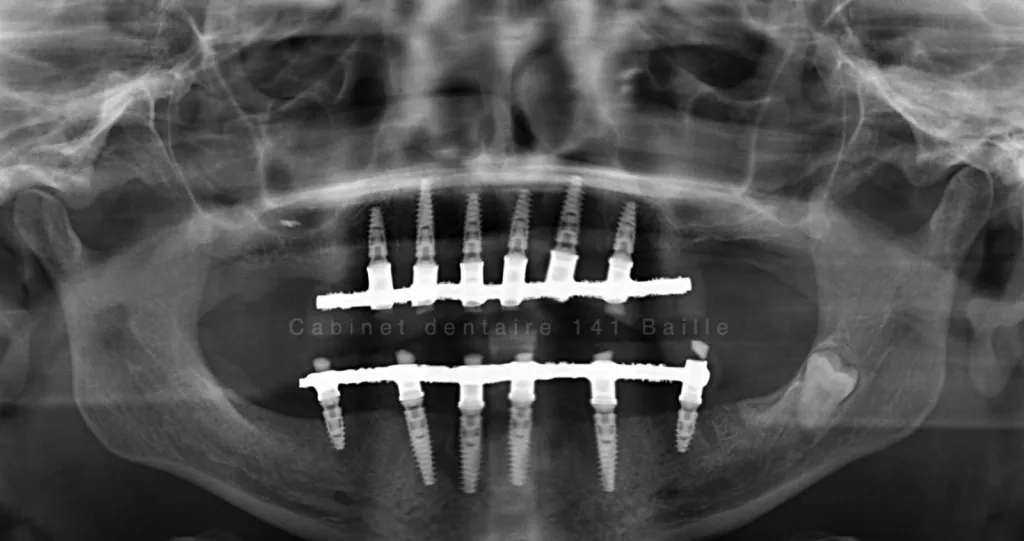

Techniques de mise en charge immédiate des implants à Marseille Cabinet 141 Baille

Le jour de l'intervention tous les implants seront mises en place les Greffes osseuses seront effectuées ,les piliers implantaires  seront connectés et une prothèse complète sera réalisée le jour même et vissé sur les implants.